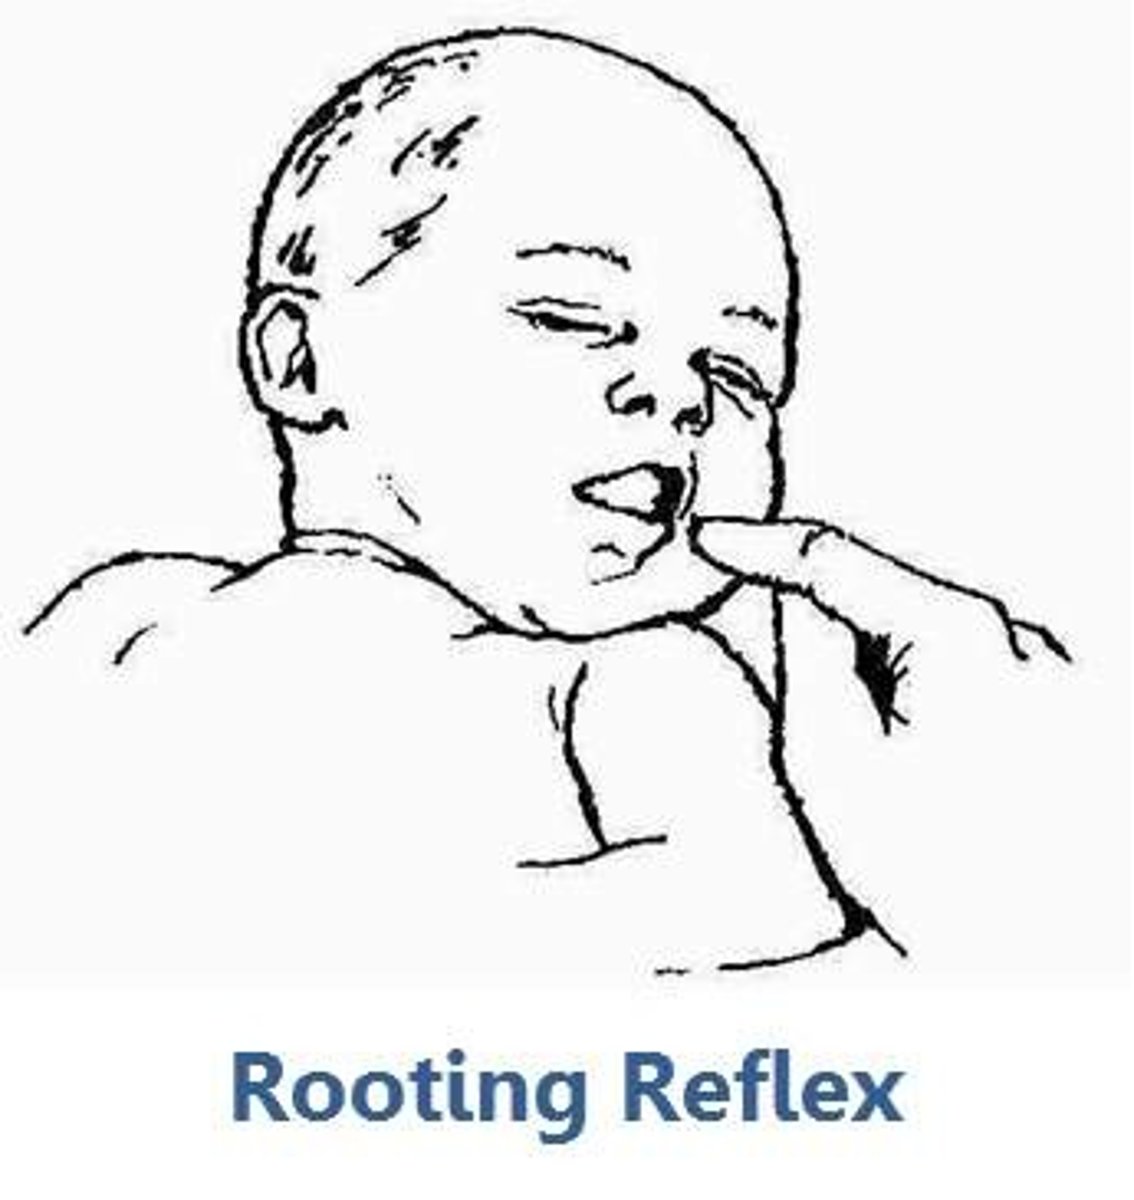

Which reflex is elicited by stroking the infants cheek, resulting in their head turning in the direction (preparing to suck)

ROOTING

Birth - 3 mo